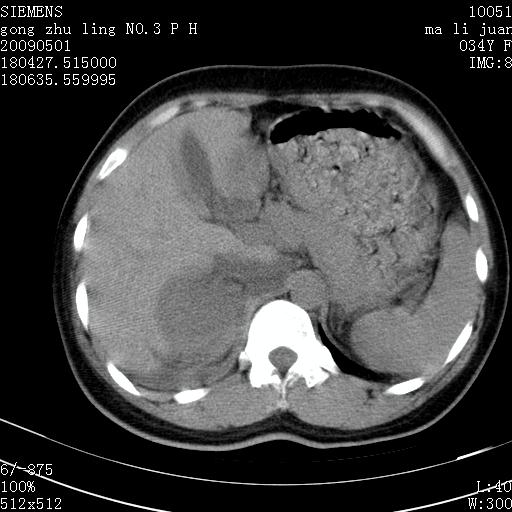

标题: CT19733:右肾碎裂

青年女性,骑摩托车摔伤。

右肾碎裂伤,包膜下血肿。

术中仅见右肾碎裂,肾蒂血管未见断裂。

支持 右肾破裂伴肾包膜下及肾周血肿。

右肾破裂并右侧腹膜后间隙出血。

右肾破裂伴肾包膜下及肾周血肿。